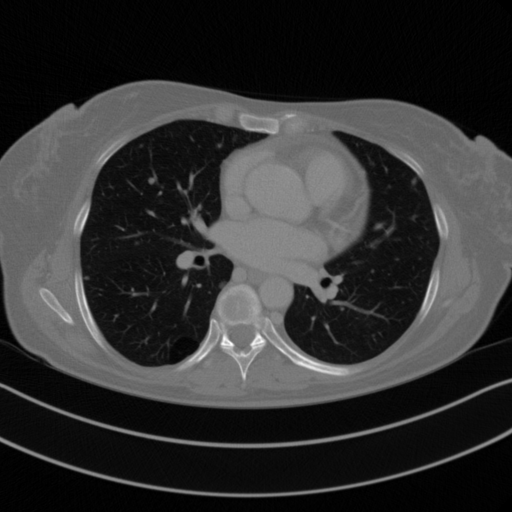

Original VENOUS CT scan

Mediastinum window (WL 40, WW 400 β†’ Low βˆ’160, High +240)

Actual HU range: [-160.0, 240.0]